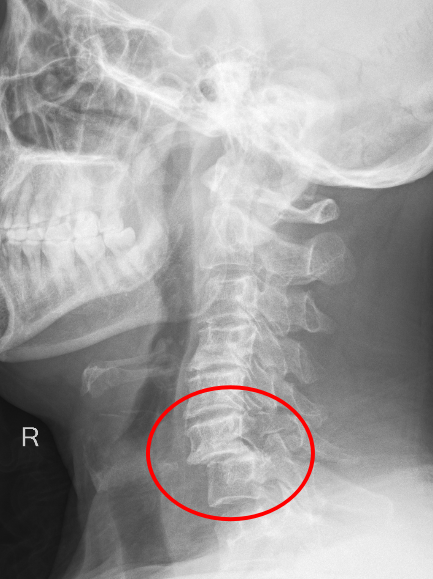

患者朱先生因意外从高处坠落,颈部剧痛、四肢麻木无力,急诊入院后经CT及MRI检查确诊为第6颈椎骨折脱位伴脊髓损,随时可能引发呼吸衰竭或永久性瘫痪。传统保守治疗风险极高,骨科主任彭李华主任医师及脊柱专业组长张利强,迅速组织多学科会诊,结合国际最新指南与患者个体情况,果断制定“前路颈椎间盘切除+植骨融合内固定术”方案,以微创技术最大限度减少神经损伤,脊髓受压明显减轻,重建颈椎稳定性。

术后影像显示,颈椎序列完美复位,内固定位置精准,患者次日即感双上肢麻木缓解,肌力较术前明显改善,术后第二天,患者颈部及双上肢疼痛症状消失,在颈托保护能自主下床行走,术后一周痊愈出院。